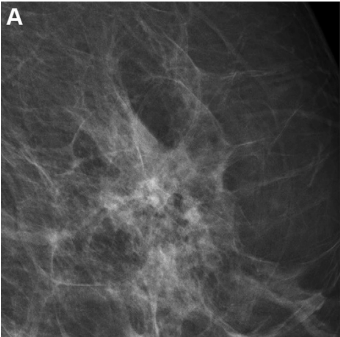

In a large retrospective study involving over 523,000 digital breast tomosynthesis (DBT) exams and over one million digital mammography (DM) exams, researchers found that DBT was associated with significantly lower recall rates but showed no advantage over DM in the diagnosis of interval or advanced breast cancer.